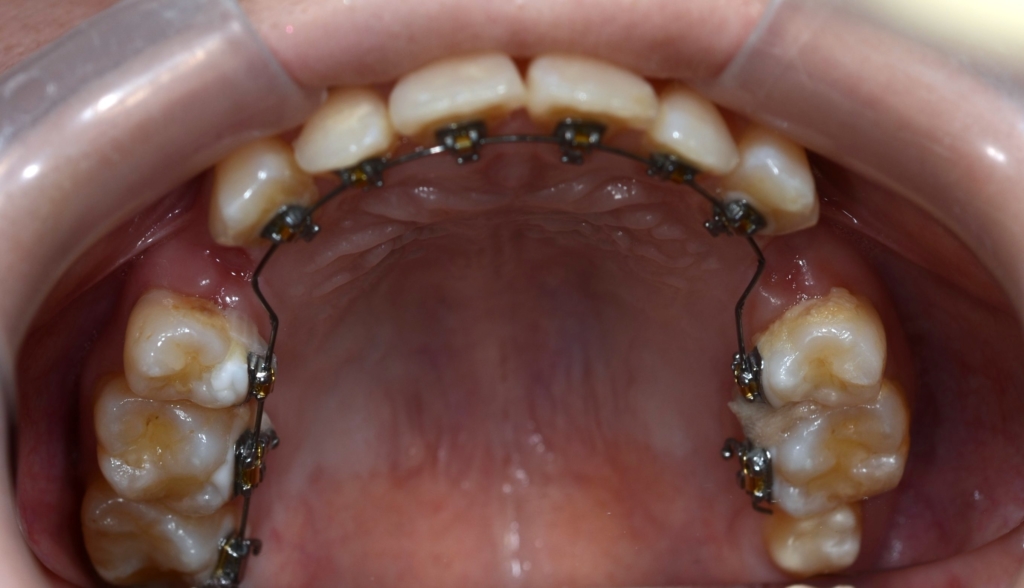

ついでに、歯並びの比較です

上段が矯正治療前、下段が矯正治療後